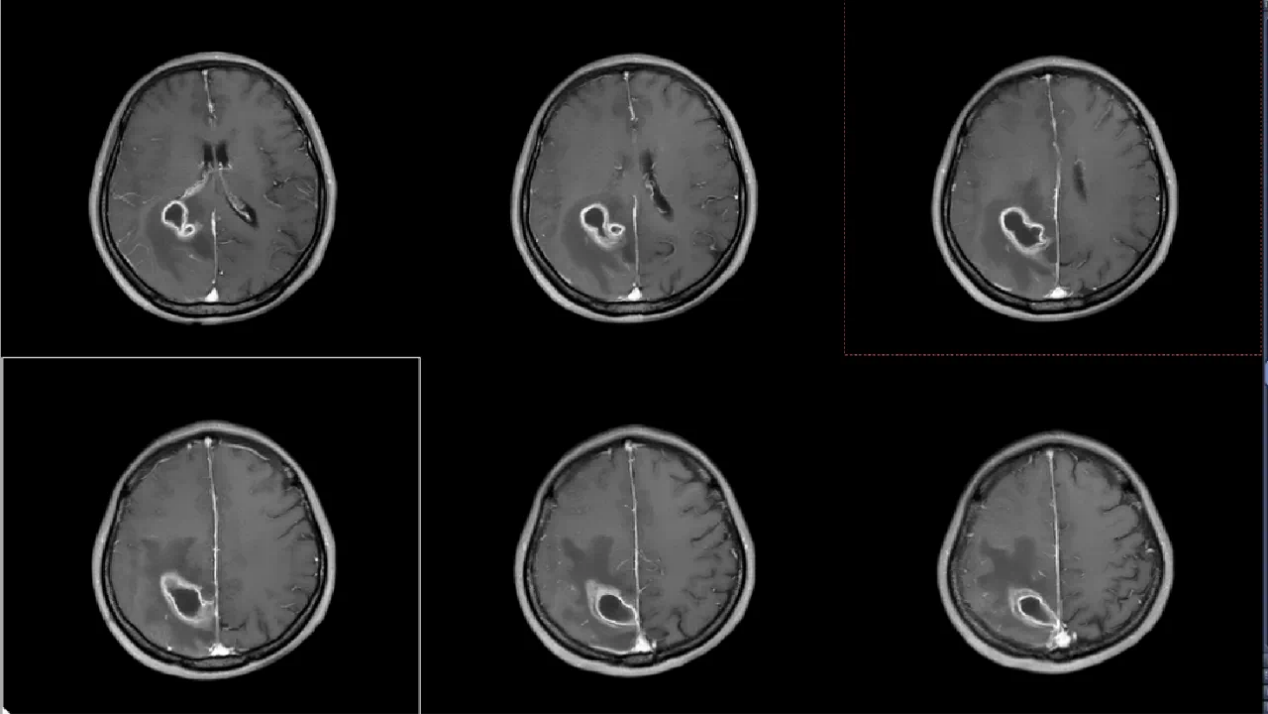

患者李女士自诉约2天前无明显诱因出现头痛,疼痛性质为阵发性胀痛,可自行缓解,伴有左侧肢体乏力,行走不稳。在本地医院检查后诊断:右侧顶叶占位性病变并周围脑组织水肿。为进一步治疗,来到南溪山医院就诊,完善各项检查后确诊为:功能区脑脓肿。

面对李女士的病情,神经外科团队经过反复讨论,决定采用机器人辅助实时可视化抽吸微创手术。手术前,团队通过3D影像重建技术,为李女士的脑部构建了精准的三维模型,清晰标注出脓肿的大小、形态以及与周围血管、神经的位置关系。手术机器人则根据这些数据,自动规划出最优穿刺路径,误差可控制在0.5毫米以内。

在机器人“导航”系统的引导下,神经外科主任王文波主任医师手持穿刺针,沿着预设路径稳步推进。术中,实时影像系统如同“透视眼”,清晰显示穿刺针的位置和脓肿内部情况,医生可以动态观察抽吸过程,确保每一步操作都精准无误。传统开颅手术需要打开十几厘米的切口,创伤大、恢复慢,还可能引发感染。而机器人辅助手术不仅创伤小,还能最大限度减少对正常脑组织的干扰。术后李女士肢体功能逐渐恢复,一周后完全恢复。